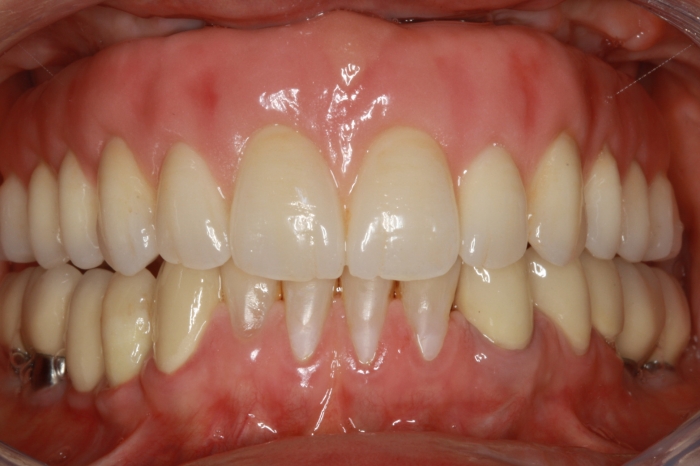

Prótese fixa em porcelana sobre implantes

Imagens da prótese fixa em porcelana e zircônia sobre implantes, do caso terminado em Fevereiro 2012